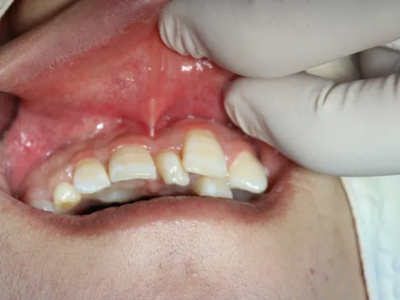

阻生牙是指由于邻牙、骨或软组织的阻碍而只能部分萌出或完全不能萌出,且以后也不能萌出的牙。引起牙阻生的成因,主要是由于颌骨缺乏足够的空间容纳全部恒牙。常见的阻生牙为下颌第三磨牙、上颌第三磨牙及上颌尖牙。

阻生牙可反复引起冠周炎,或引起邻牙牙根吸收和破坏,位置不正,不能完全萌出,好发部位是上、下颌第三磨牙。

对于阻生牙的处置需要首先明确阻生牙齿发育情况是否正常,对于由于早期外伤或其他原因造成发育异常,如牙根弯曲、短根等情况的阻生牙,还应根据患者的综合情况,决定牙齿是否保留。